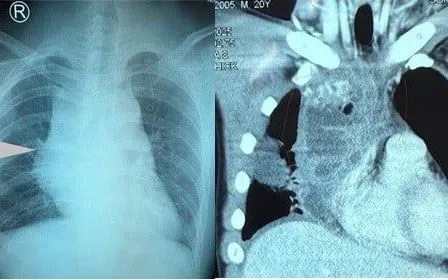

Tại Bệnh viện Nhân dân 115, kết quả chụp CT ngực có cản quang cho thấy khối u trung thất kích thước 10x7x7cm, chèn ép vào tim, phổi và tĩnh mạch chủ, gây xẹp phổi thụ động. Người bệnh được chỉ định phẫu thuật mở ngực cắt bỏ khối u dưới gây mê nội khí quản.

Theo BS.CKII Dương Văn Mười Một, Trưởng khoa Phẫu thuật tim - Lồng ngực mạch máu, u quái trung thất là u tế bào mầm hiếm gặp, thường phát triển chậm, triệu chứng chủ yếu do chèn ép tim phổi hoặc mạch máu lớn.

CT và MRI là phương tiện chẩn đoán hình ảnh quan trọng giúp xác định vị trí, kích thước và cấu trúc khối u, từ đó lựa chọn phẫu thuật cắt bỏ triệt để, phương pháp điều trị tối ưu hiện nay.